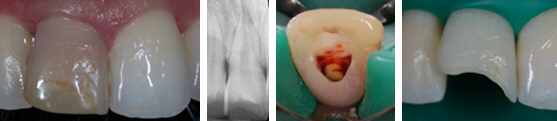

Incisivo centrale necrotico

e discolorato.

Il dente è stato trattato endodonticamente, sbiancato e ricostruito con resina

composita.